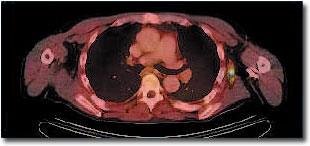

PET/CT

Bei einem Patienten mit Non-Hodgkin- Lymphom (Lymphknotenkrebs) wurde nach der Chemotherapie eine PET/CT durchgeführt. In der Achsel wird in der PET eine Lymphknotenmetastase sichtbar, die in der CT allein nicht zu erkennen ist. Anhand der PET/CT-Kombinationsaufnahme lässt sich die Metastase exakt lokalisieren. |